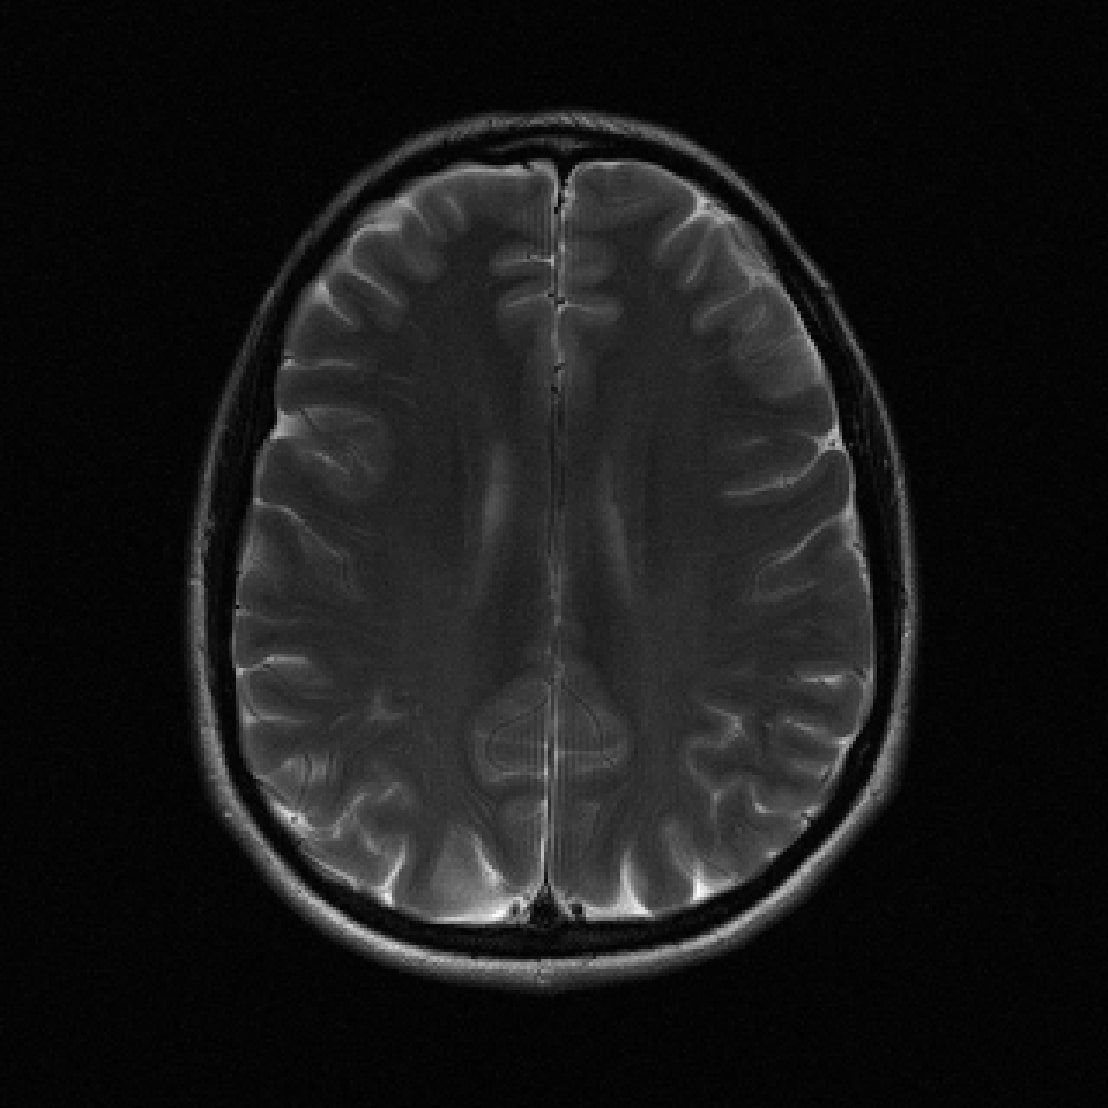

Many of our experiments are based on splits of the fastMRI dataset \citepzbontarFastMRIOpenDataset2019a, the most commonly used dataset for MRI reconstruction research. Figure 2 depicts samples from the fastMRI dataset and shows that MRI data vary in appearance across different anatomies and image contrasts (T1, T2, etc.). The image distribution also varies across vendors and magnetic field strengths of scanners, as the strength of the magnet impacts the signal-to-noise ratio (SNR), with stronger magnets leading to higher SNRs.

The fastMRI dataset stands out for its diversity and size, making it particularly well-suited for exploring how different data distributions can affect the performance of deep learning models for accelerated MRI. In our experiments in Section 3, 4, 5, and 6 we split the fastMRI dataset according to different attributes of the data. In Section 7, we showcase the generalizability of our findings on a diverse collection of 17 different datasets.

We consider two distributions and , and train U-nets \citepronnebergerUNetConvolutionalNetworks2015a, ViTs \citepdosovitskiyImageWorth16x162021b and end-to-end VarNets \citepsriramEndtoEndVariationalNetworks2020b on data from distributions and on data from distribution separately. We also train the same models on data from and , i.e., . We then evaluate on separate test sets from distribution and . We consider the end-to-end VarNet because it is a state-of-the-art model for accelerated MRI, and consider the U-net and ViT as popular baseline models. This diverse selection of architectures (unrolled, convolutional, transformer) aims to demonstrate that our qualitative results are independent of the specific architectural choice. We consider the following choices for and , which are subsets of the fastMRI dataset specified in Figure 2:

We are given data from two distributions and , where distribution can be split up into sub-distributions . We consider the following choices for the two distributions, all based on the knee and brain fastMRI datasets illustrated in Figure 2: